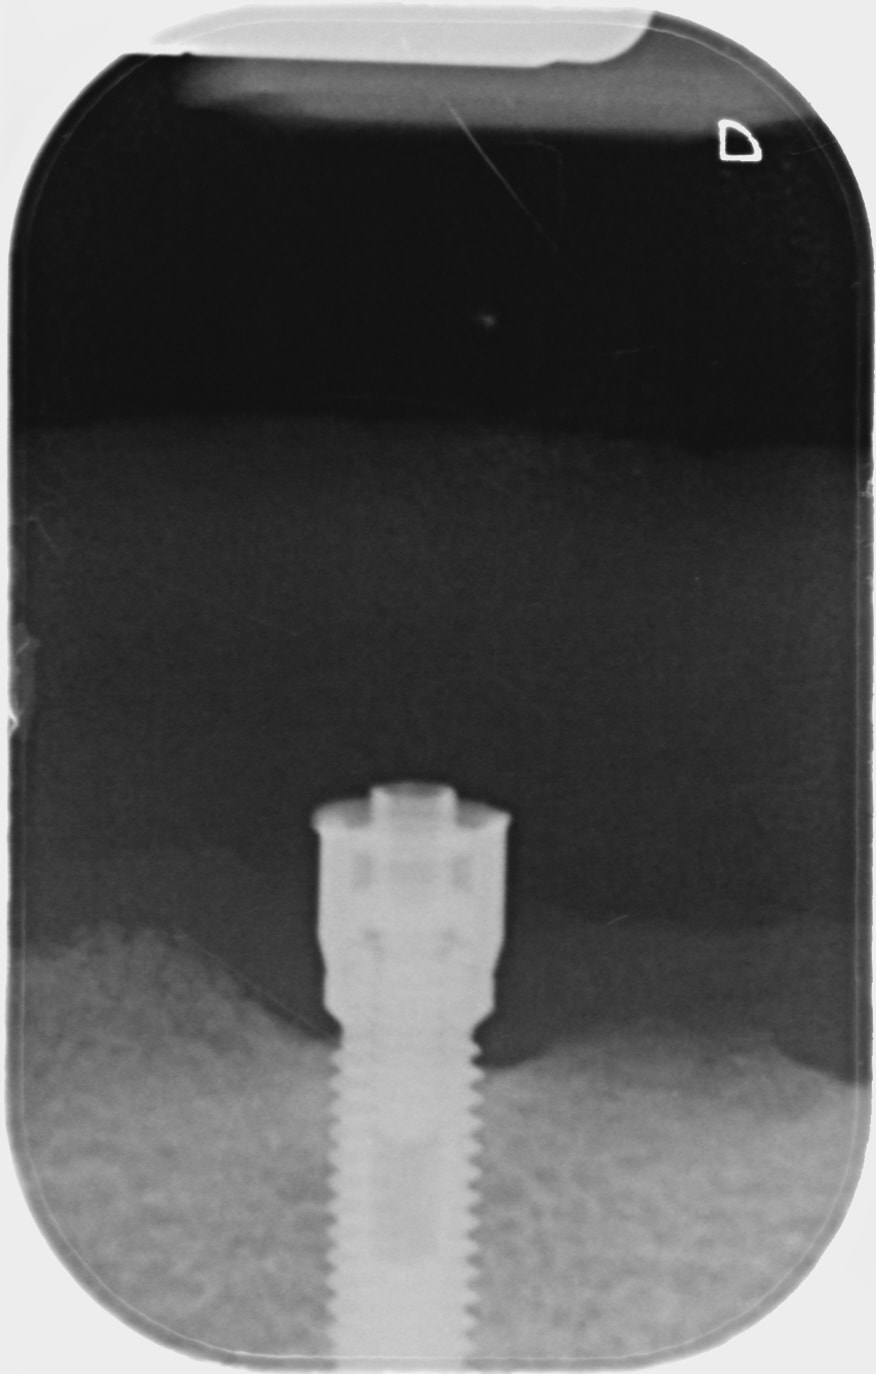

cette patiente a une PAC retenue par une barre supportée par 2 implants.

J'aimerais réutiliser ses implants pour lui proposer une solution.

Je vous joins également une photo de l'attachement, au cas où quelqu'un a une idée de ce que c'est, car il va falloir le dévisser pour exploiter l'implant.

(Désolé pour la rétro, je n'ai pas pu obtenir l'apex, peut-être que la pano pourra aider )

Nobel, mk1 je pense….mais peut importe c’est la même connexion hexagonale externe

Ça colle bien MK1 vu que les implants ont 40 ans ( c’est vrai que l’hexagone externe est le plus probable dans ce genre de cas)